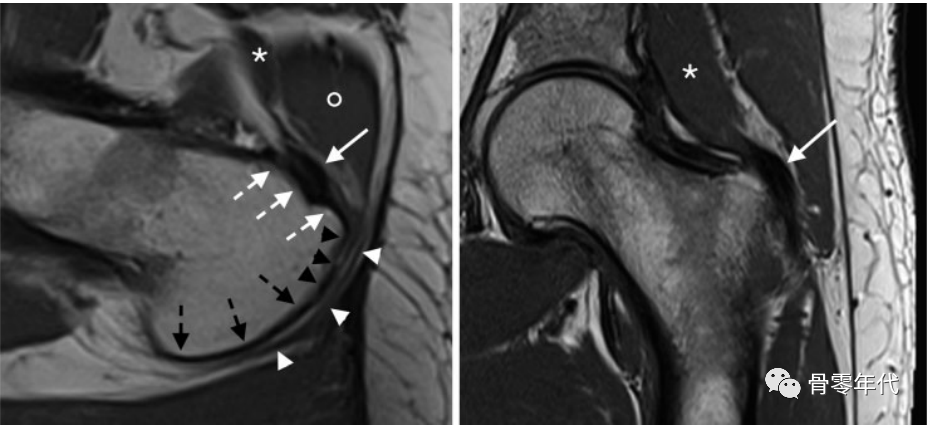

(A)56岁男性的轴位T1加权图像显示前(白色短箭头)、侧(黑色箭头)和后面(黑色短箭头)。臀小肌腱(白色箭头)插入大转子的前小关节。注意臀小肌(星号)和臀中肌(圆)之间的密切关系。粗隆间囊(白色箭头)通常不膨胀,覆盖外侧和后侧小关节。(B)冠状面T1加权图像显示臀小肌腱长头(箭头)和臀小肌(星号)在前小关节的广泛附着点。

一位29岁女性的MR关节造影。(A)矢状位T1加权像显示臀小肌腱(白色虚线箭头)附着于臀小肌腱的前小关节,臀中肌腱的后束(白色箭头)附着于大转子的上后小关节。(B)冠状面T1加权图像显示肌腱从下表面伸出的外侧束(白色箭头)。这块肌肉与肌腱一起插入大转子的远端(c,不同的患者)。注意:无任何肌腱插入臀中肌腱后的秃点(b,黑色箭头)。